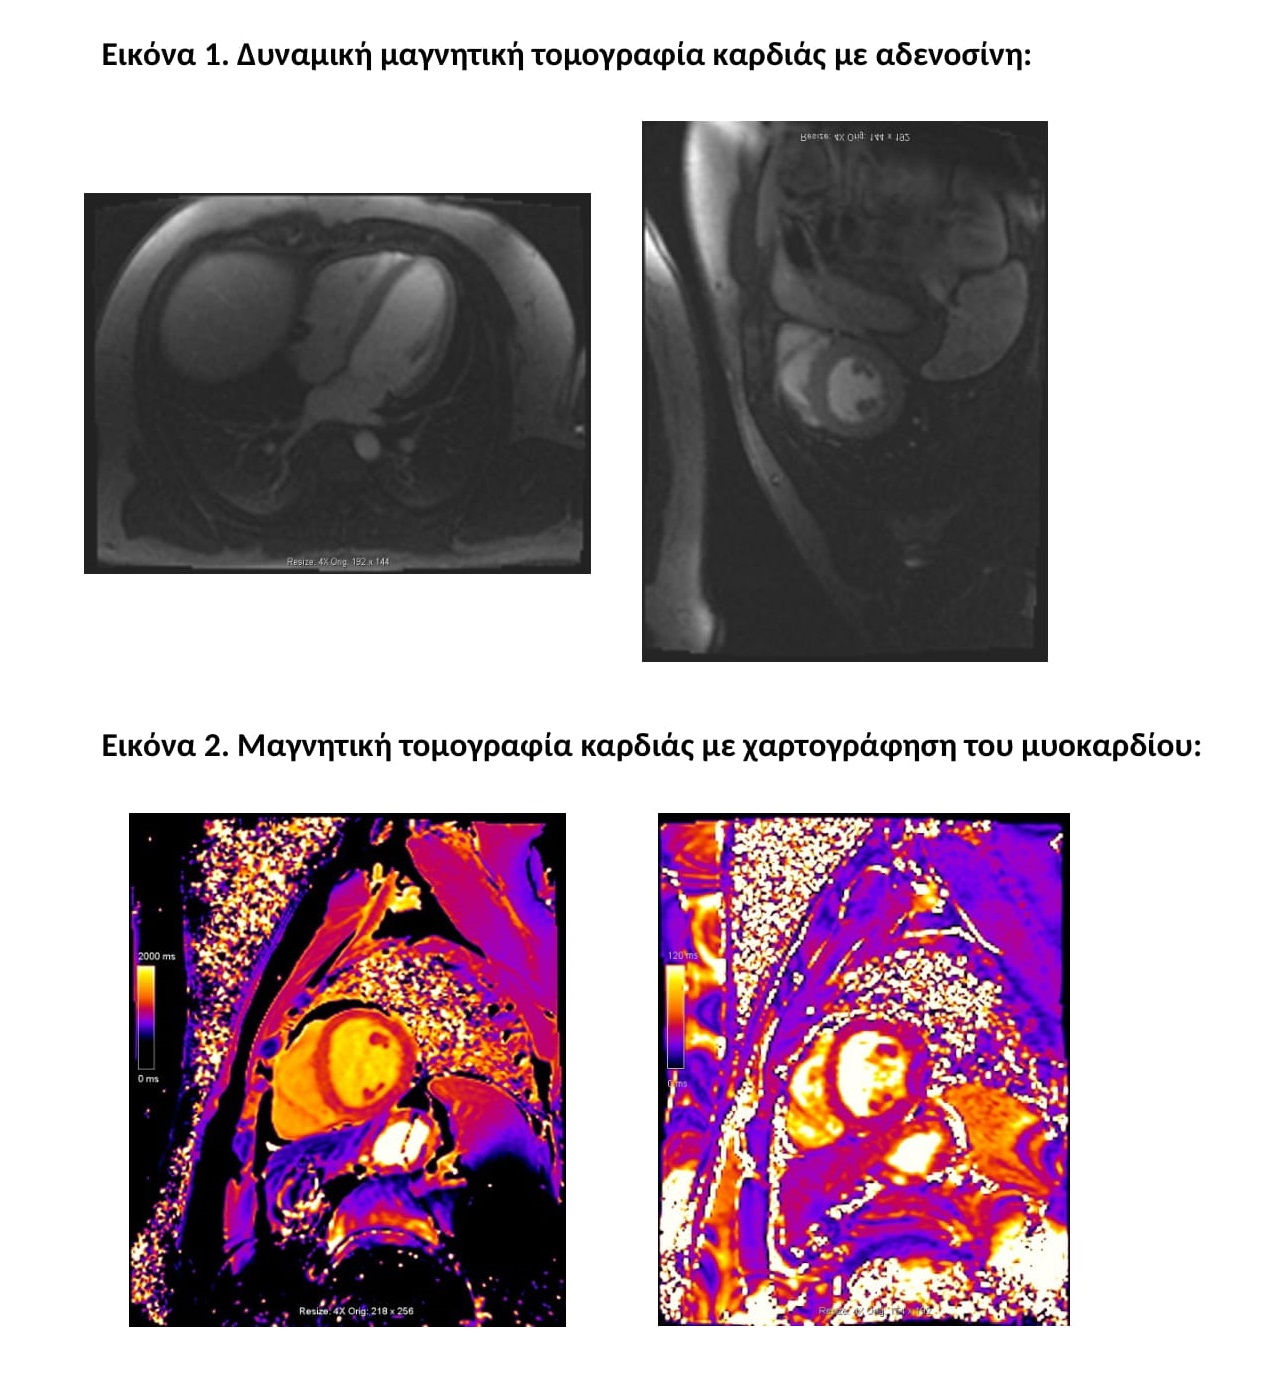

Οι νεότερες τεχνικές που εφαρμόζονται στο Τμήμα Μαγνητικής Τομογραφίας Καρδιάς του Μetropolitan Hospital είναι η δυναμική μαγνητική τομογραφία καρδιάς με αδενοσίνη (adenosine stress perfusion MRI), μια δυναμική τεχνική με υψηλή ειδικότητα, ευαισθησία, διακριτική ικανότητα και ασφάλεια και η μαγνητική τομογραφία καρδιάς με χαρτογράφηση του μυοκαρδίου (Τ1/Τ2 mapping MRI), μια συμπληρωματική απεικονιστική μέθοδος που δίνει περισσότερες πληροφορίες με ασφάλεια σε περιπτώσεις αντένδειξης της χρήσης σκιαγραφικού ενδοφλεβίως.

Τα βασικότερα πλεονεκτήματα της δυναμικής μαγνητικής τομογραφίας καρδιάς με αδενοσίνη (adenodine stress perfusion MRI) είναι η υψηλότερη ευαισθησία και ειδικότητα σε σχέση με τις υπόλοιπες διαγνωστικές μεθόδους δυναμικής απεικόνισης (σπινθηρογράφημα μυοκαρδίου, stress echo), η καταγραφή ακόμα και μικρών υπενδοκάρδιων ισχαιμικών περιοχών και μυοκαρδιακών ουλών, η καλύτερη διακριτική ικανότητα σε σχέση με το σπινθηρογράφημα του μυοκαρδίου και η ασφάλεια λόγω της απουσίας έκθεσης σε ιονίζουσα ακτινοβολία (εικόνα 1).

Η χαρτογράφηση του μυοκαρδίου με Τ1 και Τ2 ακολουθίες βοηθά στον γρήγορο, χωρίς τη χρήση σκιαγραφικού παράγοντα και ασφαλή χαρακτηρισμό του μυοκαρδίου και ανιχνεύει περιοχές με μυοκαρδιακό οίδημα και μυοκαρδιακή βλάβη όπως η ίνωση. Γίνεται συμπληρωματικά των κλασικών ακολουθιών της μαγνητικής τομογραφίας καρδιάς και προσφέρει πρόσθετες πληροφορίες για τυχόν βλάβες στο μυοκάρδιο ειδικά σε εξετάσεις όπου υπάρχει αντένδειξη στη χορήγηση ενδοφλέβιου σκιαγραφικού όπως είναι η κύηση ή προϋπάρχουσα αλλεργία (εικόνα 2).